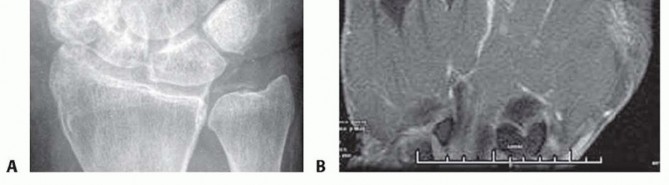

Radiographic evaluation begins with orthogonal plain films. Early in the disease process, radiographs are typically normal or demonstrate only subtle soft tissue swelling and joint space widening secondary to effusion. However, they are crucial for ruling out retained radiopaque foreign bodies, fractures, or underlying chronic arthropathies. The presence of chondrocalcinosis, for instance, may suggest pseudogout, though crystalline arthropathy and septic arthritis can coexist.

When the diagnosis remains equivocal, or to assess the extent of soft tissue and osseous involvement, Magnetic Resonance Imaging (MRI) is the modality of choice. MRI provides unparalleled soft tissue contrast, readily identifying joint effusions, synovial hypertrophy, and early marrow edema indicative of impending osteomyelitis. T2-weighted fluid-sensitive sequences will dramatically highlight the intra-articular purulence and surrounding inflammatory edema.